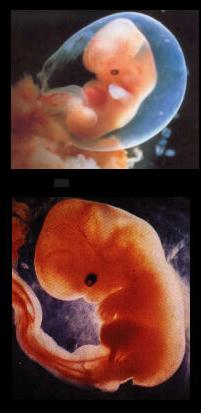

4 haftalık bebek görüntüsü 25 haftalık bebek 25 görüntüsü

anne karnında 4 haftalık

anne karnında 4 haftalık